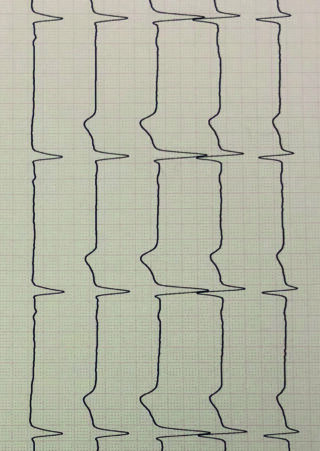

Studienarbeit

Cameraroll, Dennis Kahveci

Organ in meinem

Körper, dass

ununterbrochen

arbeitet, um mich

buchstäblich am

Leben zu erhalten.

Diese ausgewählte

Bilder sind aus den

letzten 3 Jahren und

zeigen wie ich mich

visuell mit meiner und

anderer Haut

auseinander gesetzt

habe.